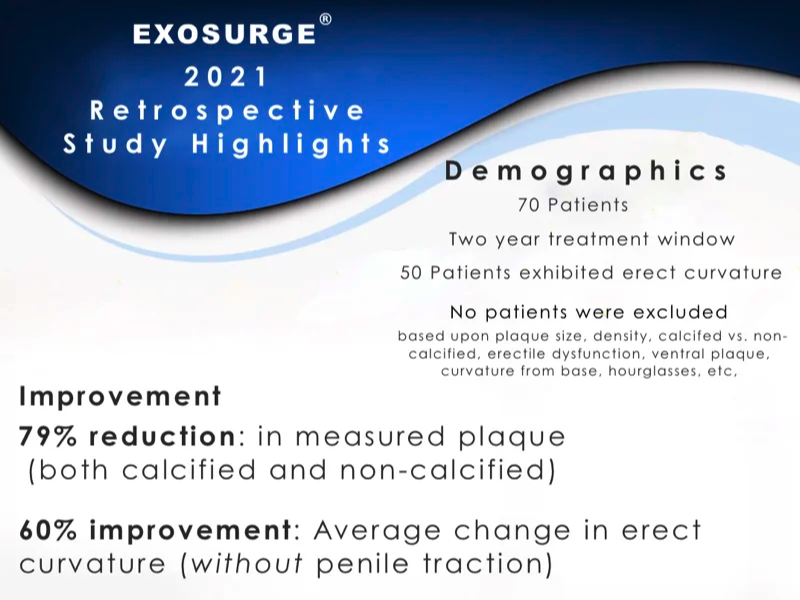

Highlights of ExoSurge® 2021 Retrospective Study

Highlights: Calcified Plaque Before & After Sonogram Images

Following is a set of four "before and after" duplex sonogram images of Peyronie's patients with calcified plaques